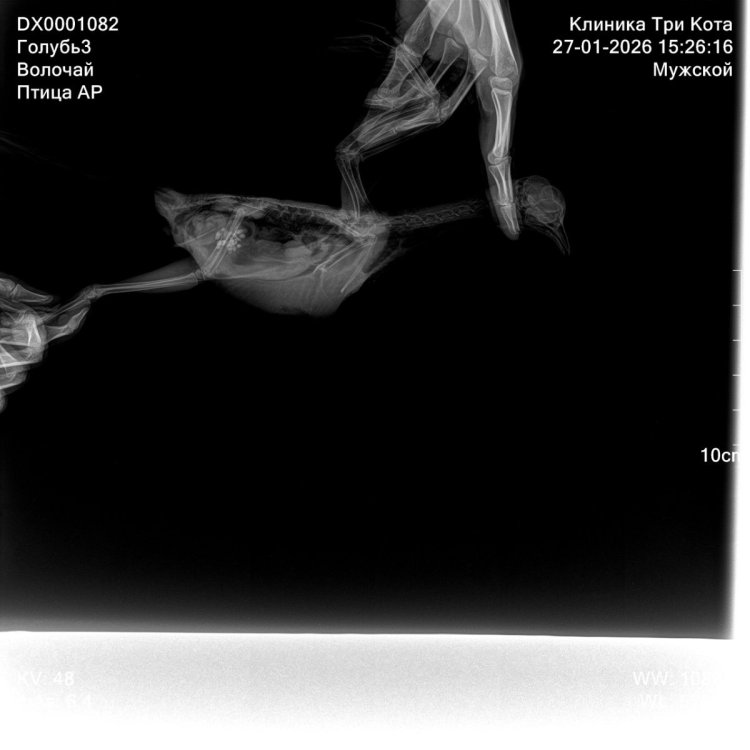

@свс у нас брали помет на анализ, но не включили его в стоимость, так как «там ничего такого, бактерии как и у всех уличных». Спасибо на этом 😂 и дополнительно взяли анализы на сальмонеллез и микобактериоз (анализов еще нет) честно немого в шоке с неправильных доз, потому что мы именно к ней всегда ездим и по ее дозам лечимся Это вот что мы делали микроскопия кала не включена но сделана пошла фоткать все что вы написали

рентген покажите @Zosia